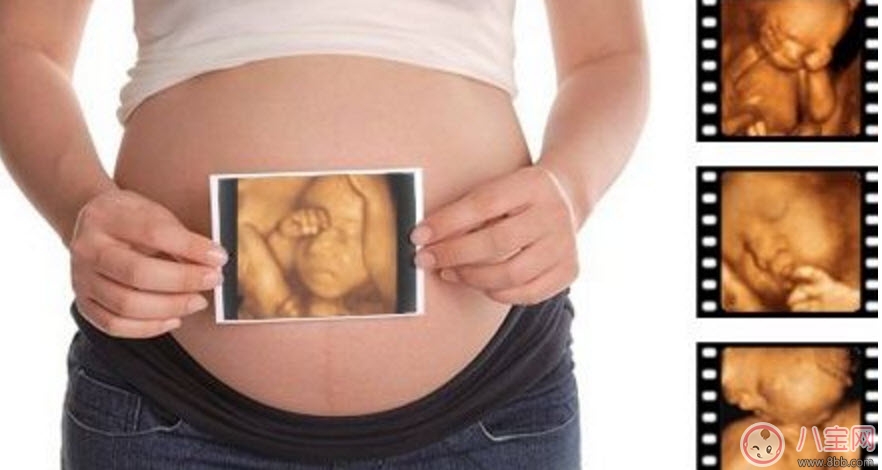

孕婦的羊水適量的話就可以做這項(xiàng)檢查。但是受胎兒體位、胎盤以及孕期不同等方面的因素影響,專家建議最佳做四維彩超的時(shí)間應(yīng)該是12-30周,這個(gè)時(shí)期就可以完全獲取到胎兒的面部以及身體等結(jié)構(gòu)的圖像。懷孕十個(gè)月的時(shí)候里最少要做3次的四維彩超,時(shí)常觀察胎兒成長。

第一次檢查:選擇懷孕14周左右

選擇在懷孕4個(gè)月的時(shí)候做四維彩超檢查。在這個(gè)檢查過程中,可以觀察到胎兒的頭、體、以及四肢的整體圖像,觀察時(shí),醫(yī)生也會(huì)特別注意胎兒的整體活動(dòng)是否協(xié)調(diào)。協(xié)調(diào)的話表示胎兒生長的很健康,當(dāng)然不協(xié)調(diào)的話也是可以接受治療改善的,這個(gè)時(shí)候還有時(shí)間。

第二次檢查:選擇懷孕22周左右

孕婦在懷孕5個(gè)多月的時(shí)候做四維彩超檢查。在觀察時(shí),可以明顯的看到胎兒要比上次觀察的要大,而且在同一幅圖像上還不能完全地顯示出胎兒的全部結(jié)構(gòu)??梢酝ㄟ^局部的觀察胎兒是否健全,有沒有一些其他癥狀的出現(xiàn)。如果真的這樣,胎兒很大的可能會(huì)是畸形生長的、發(fā)育明顯不健康。

第三次檢查:懷孕28周左右

懷孕7個(gè)月左右也是做四維彩超檢查的好時(shí)機(jī)。這個(gè)時(shí)期的胎兒的皮下脂肪、面部表情都會(huì)比較飽滿、清晰。同時(shí)還可以看到胎兒在母體中的形體動(dòng)作以及面部表情。這個(gè)階段的檢查對于胎兒的發(fā)育是否正??梢愿用鞔_。這對懷孕晚期的胎兒健康尤其重要,所以必須好好做詳細(xì)的檢查。